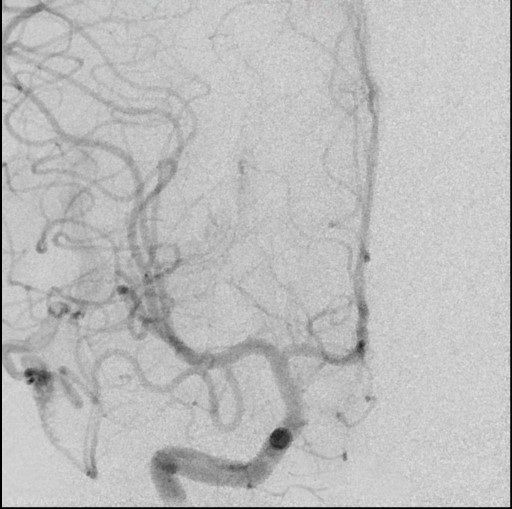

Diagnóstico de Malformação Arteriovenosa Cerebral após Traumatismo Craniano

Images in Pediatrics